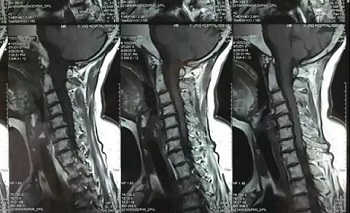

九、翻拍磁共振图像时,因为磁共振片子很大,而且一张片子上有很多图像(如下图),所以,单纯的拍一张片子,因为手机拍摄,像素以及翻拍质量不好,且放大后图像会发虚,细节看不清楚,所以,基本上是没用的,对于医生阅片来说,质量太差,不能获取图片上的有效信息。

十、因此需要将磁共振的一张片子,进行分区域局部放大拍摄,尽可能的将片子上的细节拍摄清楚,将一张磁共振片子进行分区。

十一、将分区的磁共振图像,按顺序进行拍摄,即可获取如下比较有价值的清晰图片